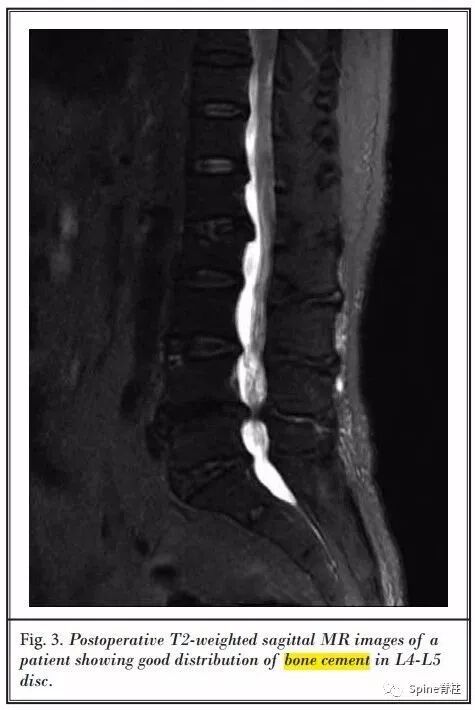

随后,P.P. Varga团队又进行了一项研究,发表在2019年的Eur Spine J上。

他们发现,PCD治疗严重腰椎间盘退行性疾病引起的轴性腰痛和功能障碍是一种有效的微创方法。同时,术后可以纠正腰椎畸形,并达到椎间孔的间接减压的效果。尤其适合于不易行开放手术的老年患者。

-

术后骶骨倾斜角和骨盆倾斜角明显减小,腰椎节段性和整体后凸、椎间盘和椎间孔高度都明显增加。VAS和ODI评分明显改善,且腰痛的改善余节段性侧凸矫正明显相关,且无明显并发症发生。

术后情况

2例退变性侧凸患者术后比较